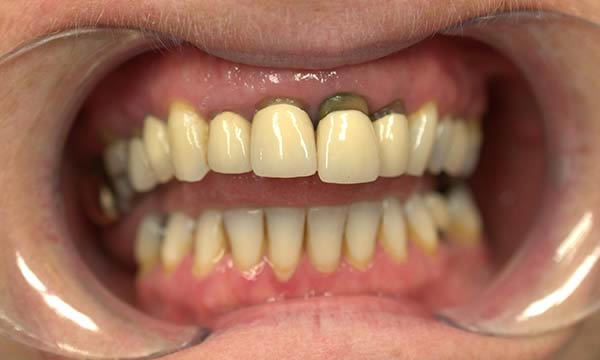

This case is a collaboration between ourselves and a specialist periodontist based in the referring practice. A case of patience, where a patient wanted to be rid of his un-retentive denture replacing the UL1 while stabilising his periodontal disease with improved home care and treatment from a specialist periodontist.

After approximately 12 months of periodontal therapy, the patient was deemed stable enough by the specialist periodontist to undergo implant treatment. An Astra EV implant was placed and a well shade matched zirconia crown was luted to an Atlantis abutment. Digital SLR pictures were used to provide the lab technician with appearance detail of the neighbouring dentition, to allow the technicians at Smile Dental Laboratory to introduce 'accents' and a realistic and seamless look to the final zirconia prosthesis.